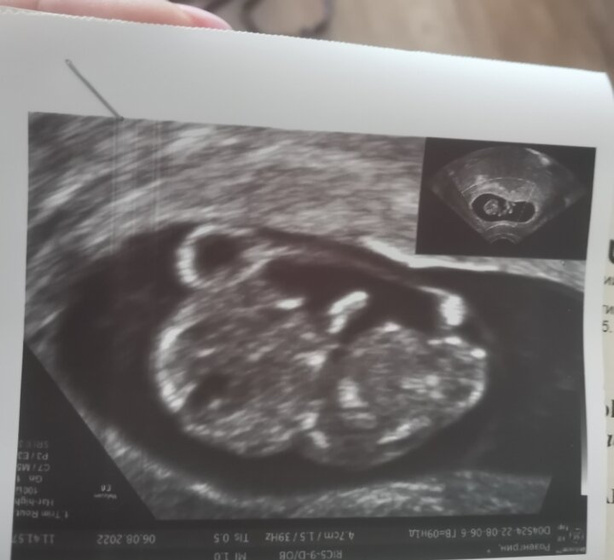

Не дождалась я 1го скрининга. Проснулась с мыслью, что сегодня нужно поехать и посмотреть как там наш малыш устроился. Все хорошо, по узи соответствует сроку по мес. 9 недель и 1 день. Я рада?